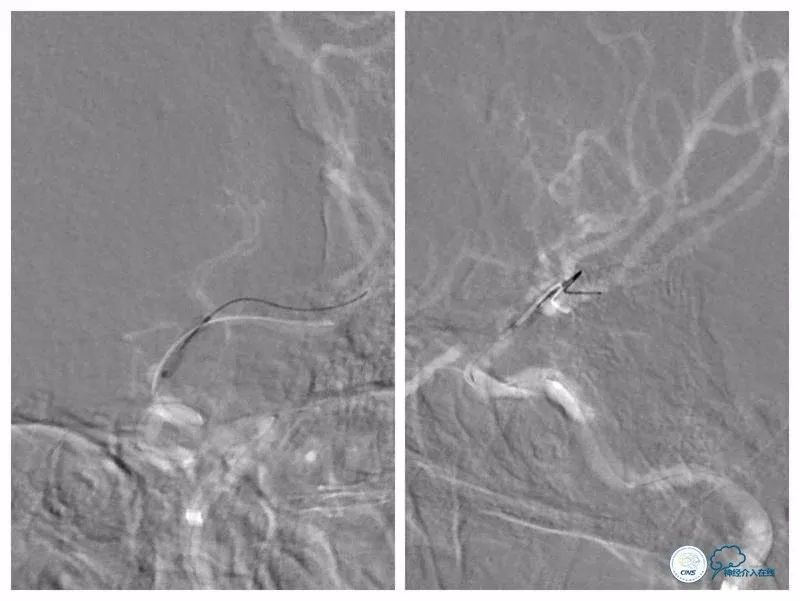

全麻下右股动脉入路,8F导引导管至左颈总动脉末端,将6F Navien导管送至左颈内动脉C1段以远,造影示左颈内动脉C6-7段长段狭窄,狭窄率约90%,长度约10mm(图7)。

图7

路径图下沿Navien导管送入Echelon 10微导管携Synchro微导丝(0.014″,200cm)尝试过狭窄段未成功(图8)。

图8

更换为Pilot-50微导丝(0.014″,200cm),越过狭窄起始段,再次更换为Synchro微导丝,送至左大脑中动脉M2段(图9)。

图9

跟进Echelon 10微导管以期通过病变未获成功,遂逐节剪断微导管撤出微导管,保留微导丝。送入Ultra-soft球囊(2.0mm×20mm)至狭窄段近端及远端行球扩后造影显示狭窄程度和前向血流均有所改善(图10)。

图10

沿导丝送入两枚Apollo(2.5mm×8mm)球扩式支架由远及近释放(图11,12)。

图11

图12

其后造影显示支架贴壁可,前向血流TICI 3级(图13)。